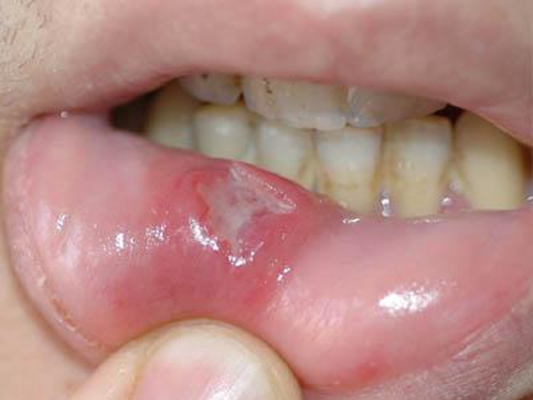

口腔癌圖片

口腔癌的前兆 (7)